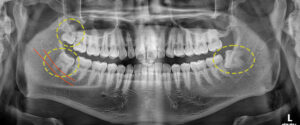

두 번째 환자분을 소개해 드릴께요.

위 환자분은 상악 좌측을 제외한

모든 곳에 사랑니를 가지고 계셨는데요.

파노라마 사진을 보시면 하악 좌측 사랑니는

치아가 수평 매복 되어 있고,

하악 우측 사랑니는 신경관을 물고

위치해 있는 것처럼 보였어요.

왼쪽 먼저 발치한 후 잇몸이 아물고 나면

반대쪽 상, 하악을 발치하기로 했으며,

마찬가지로 양쪽 모두 잇몸을 절개한 후

치아를 쪼개어 발치를 진행했어요.

발치 후 파노라마 사진을 보시면

깔끔하게 발치된 모습을 보실 수 있어요.👀

환자분께서도 마취가 풀린 후에도

큰 붓기도 없고 통증도 없었다며

만족해 하셨어요.😁